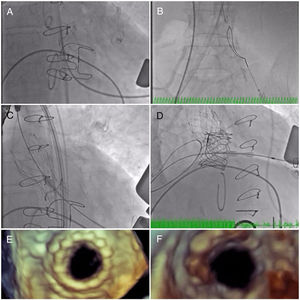

The initial plan was to implant a 23-mm CoreValve Evolut R (Medtronic, Irvine, CA) in aortic position (transfemoral approach) and a 29-mm Edwards SAPIEN 3 in mitral position (transapical approach). The procedure began with a successful left transfemoral approach with a 14-F Fast-Cath sheath, and the left coronary artery was protected with an angioplasty guidewire. Due to extreme difficulty in retrograde crossing of the aorta, a transapical-transfemoral loop approach was considered. The loop was created after gaining transapical access (Figure 2A), through which an INFINITI MPA 2 catheter (5.0 Fr×125 cm, Cordis) was used to advance an Emerald J wire (0.035″×260 cm) anterogradely until it reached the left common iliac artery, where it was captured with a 25-mm Amplatz Goose Neck snare (Figure 2B). After wire externalization at the left groin, the MPA 2 catheter was removed from the apical access and inserted via the groin, enabling the Emerald J wire to be exchanged for an Amplatz Extra Stiff guidewire (0.035″×260 cm) via a left transfemoral route (Video 2). The CoreValve was then successfully advanced into the aortic root and implanted in a suprannular aortic position under rapid pacing (Figure 2C and Video 3), 7 mm below the radiopaque Mitroflow ring. The left coronary ostium was unobstructed. Subsequently, the mitral valve-in-valve Edwards was successfully implanted transapically, without complications (Figure 2D and Video 4). Intraprocedural transesophageal echocardiography showed normal gradients (mean aortic gradient 11 mmHg, mean mitral gradient 3 mmHg) (Figure 2E and F) and a mild aortic perivalvular leak (Video 5). There were no immediate procedural complications. Due to contrast nephropathy and development of anuria (serum creatinine increased to 5.1 g/dl), the patient needed temporary renal replacement therapy, which was discontinued after two and a half weeks due to resumed diuresis. Before discharge, TTE revealed a small paravalvular aortic leak and normally functioning prosthetic valves. The patient was discharged in New York Heart Association (NYHA) functional class II on the 67th day with mild anemia (hemoglobin 11.5 g/dl), creatinine 1.0 mg/dl and eGFR 30 ml/min/1.73 m2.

(A) A long Emerald J wire passes through the stenotic Mitroflow, in which it is captured with an Amplatz Goose Neck snare (B); valve-in-valve implantation of a 23-mm CoreValve Evolut R in aortic position by the transfemoral route (C); implantation of a 29-mm Edwards SAPIEN 3 in mitral position by the transapical route (D); new aortic (E) and mitral (F) bioprosthetic valves visualized by transesophageal echocardiography during the procedure following implantation.